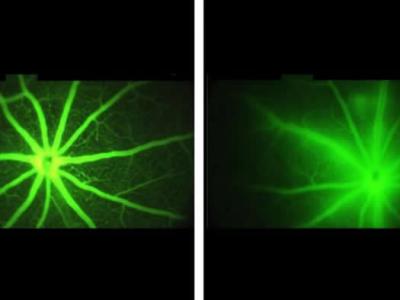

约翰.霍普金斯医疗集团研究人员发现一种

约翰.霍普金斯医疗集团研究人员发现一种试验药物治疗视力丧失...